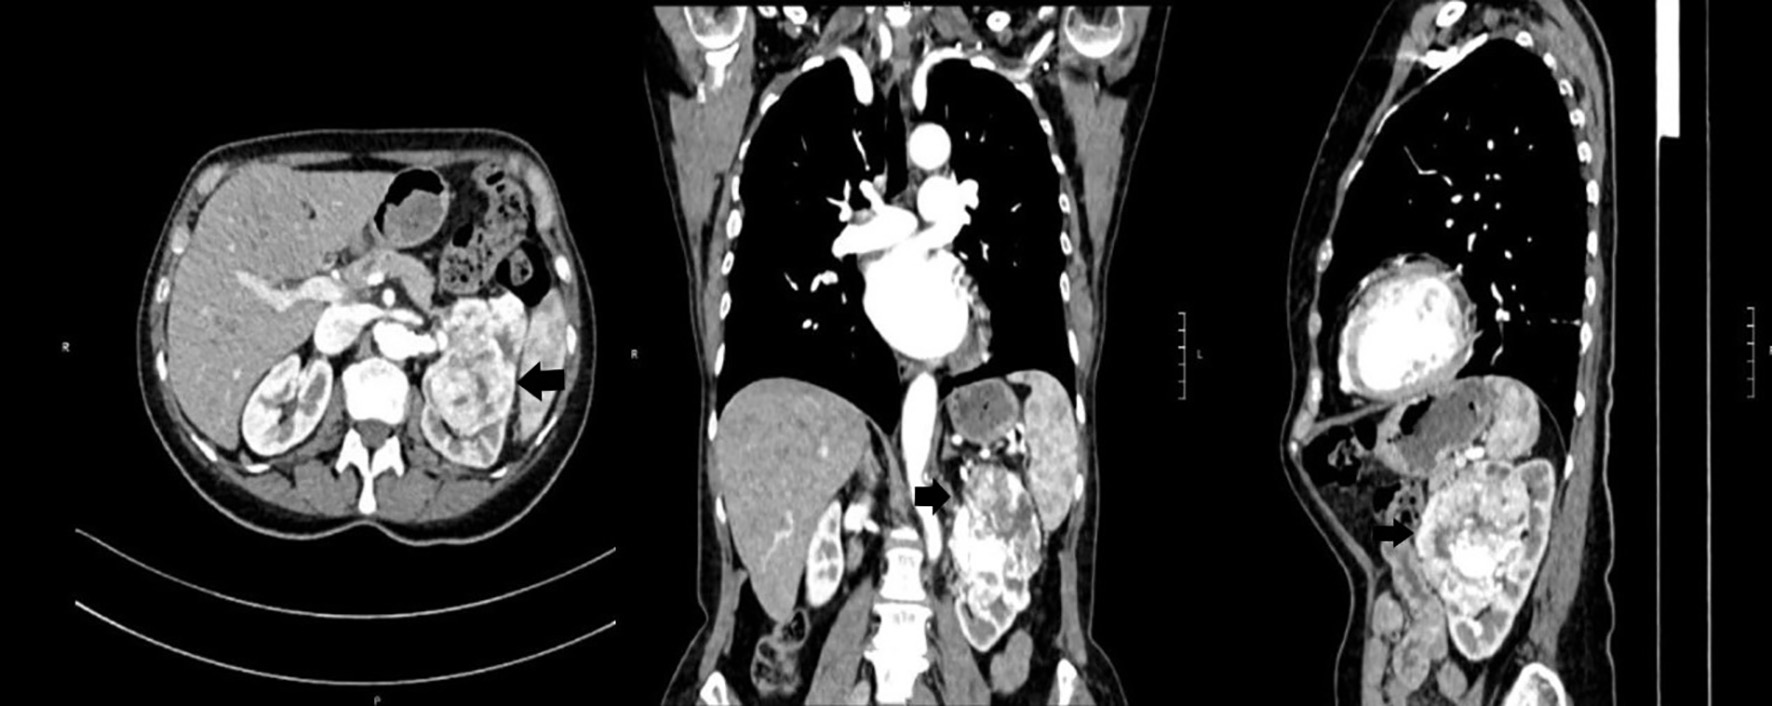

A 63-year-old female patient came to our attention for lower back pain. Her past medical history was significant for hypertension and pulmonary sarcoidosis treated with steroids. Neurological examination revealed a lumbar spinal syndrome without motor deficit. After failure of medical management, spinal computed tomography (CT) scan was performed, demonstrating a spinal lesion of 24 × 23 mm at the seventh thoracic vertebra (Fig. 1). A thoraco-abdomen CT scan revealed an 86 × 61 × 79 mm mass at the left kidney (Fig. 2) with multiple right pulmonary nodules and six bone lesions confirmed at the bone scan (Fig. 3). At diagnosis, Karnofsky Performance Status (KPS) was 80. The International Metastatic RCC Database Consortium (IMDC) risk score was intermediate and the Memorial Sloan-Kettering Cancer Center (MSKCC) score was intermediate. After multidisciplinary discussion, the patient underwent open trans-peritoneal left radical nephrectomy. The histology results described a ccRCC grade 2 with tumor extension in segmental (muscle-containing) venal branches and perirenal fat with clear margins (pathological T3aR0Nx). One month after surgery, she developed signs of spinal cord compression with neurological deficits and underwent emergency spinal decompression with a D7 laminectomy and stabilization of D5/D9. After neurosurgical operation and physiotherapy, she achieved complete remission of back pain and neurological deficits. A radiotherapy treatment of the vertebral metastases after surgery was avoided in order not to jeopardize complete functional recovery. The follow-up thoraco-abdomen CT scan after 3 months ruled out disease progression. She is currently on an immunotherapy regimen with avelumab (anti-programmed cell death-1 ligand, programmed death ligand 1) and axitinib (a vascular endothelial growth factor receptor TKI).

![]() Click for large image | Figure 2. Abdominal computed tomography scan. Arrow indicates a left renal cell carcinoma. |